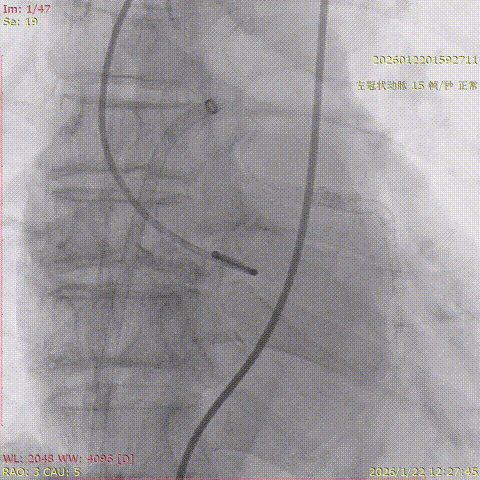

2026年伊始,TaurusTrio经导管主动脉瓣系统在复旦大学附属中山医院,浙江大学医学院附属第二医院,中国医学科学院阜外医院,首都医科大学附属北京安贞医院,四川大学华西医院等多家临床中心成功开展上市后全国首批植入。这不仅是TaurusTrio正式走向广泛临床应用的重要里程碑,更标志着中国单纯主动脉瓣反流介入治疗正式迈入了“心键合璧”的全新纪元。